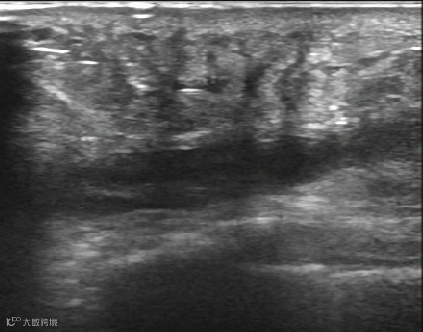

腱鞘囊肿抽液治疗:

治疗前,囊肿大小11X10mm。

治疗后,囊肿消失。